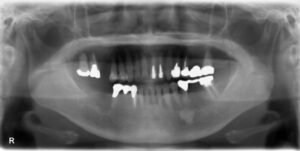

下顎臼歯2本欠損症例

BEFORE AFTER 73歳女性/下2本/インプラント埋込手術 【治療内容】 右下第一大臼歯、第二大臼歯のグラつきが…